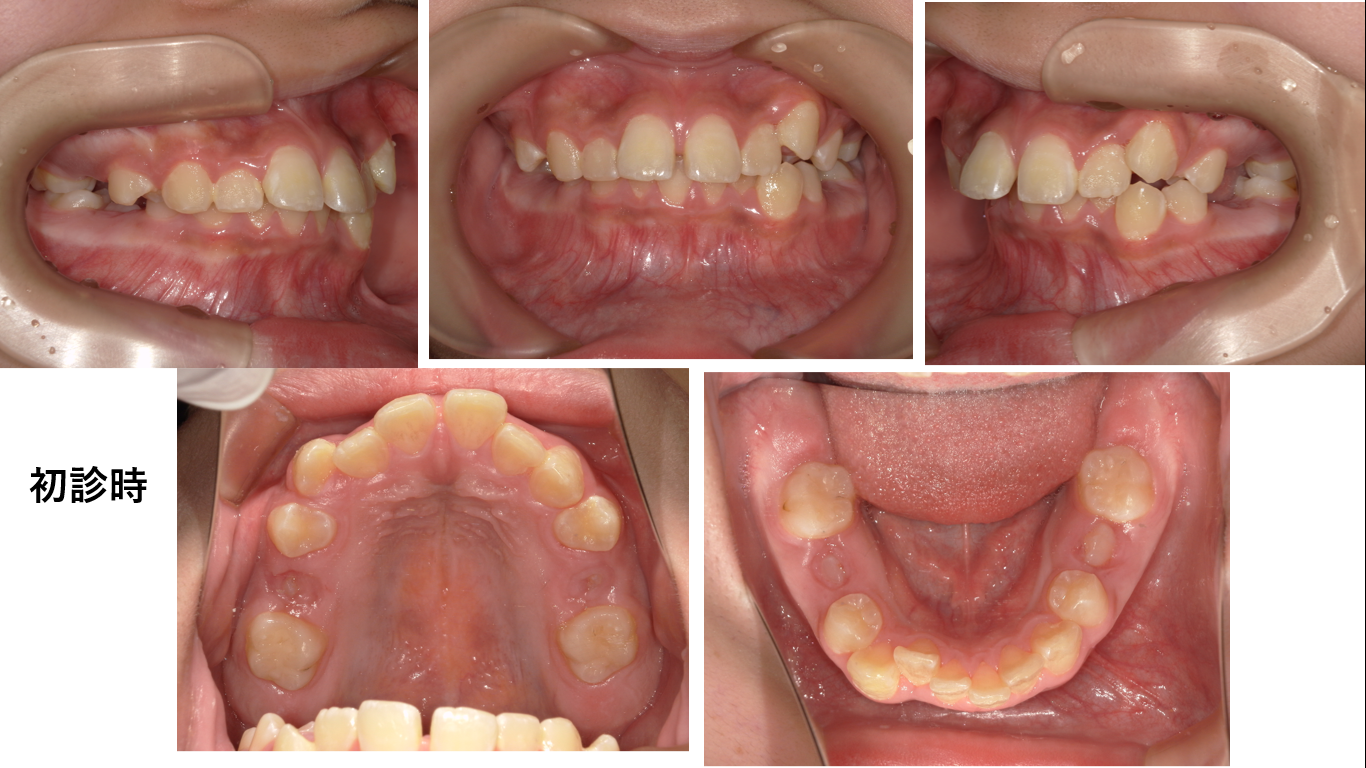

矯正症例149 AngleⅠ級上顎前突

初診時12歳 治療期間2年6か月、抜歯部位:上下顎左右4番、治療費総額112万円(税込み)